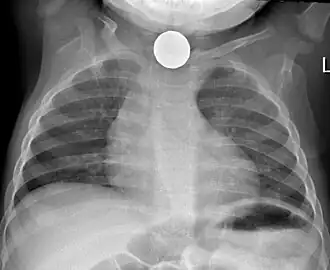

Prior to undertaking endoscopy, attempts should be made to locate the foreign body with x-rays or other non-invasive techniques.[1] For radio-opaque objects, x-rays of the neck, chest and abdomen can be used to locate the foreign body and assist endoscopy.[9] Alternative approaches, including the use of metal detectors, have also been described.[10]

X-rays are also useful for identifying the type of foreign body ingested and complications of foreign body ingestion, including mediastinitis and perforation of the esophagus.[1]